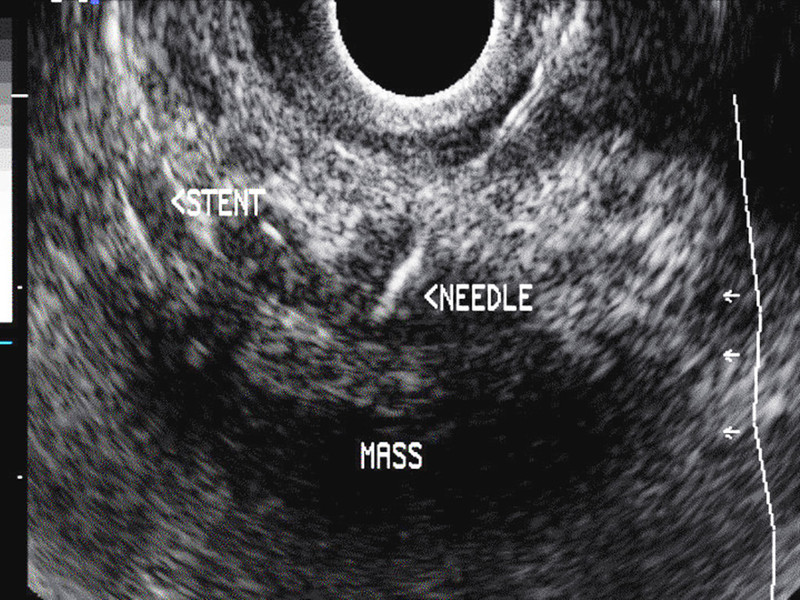

圖為胰臟癌患者接受內視鏡超音波及「細針抽吸術」(NEEDLE處)切片的影像。(photo by newsnetwork.mayoclinic.org)

研究團隊分析1千5百多名未接受切片檢查的胰臟癌患者,以及近500名接受「細針抽吸術」患者的病情變化。細針抽吸術是目前臨床上最常使用的切片方式,以乳癌為例,透過觸診、超音波或X光檢查發現異常腫塊後,將中空的細針從體外插入腫塊吸取部分細胞,再由病理實驗室分析細胞來自良性組織或惡性腫瘤。